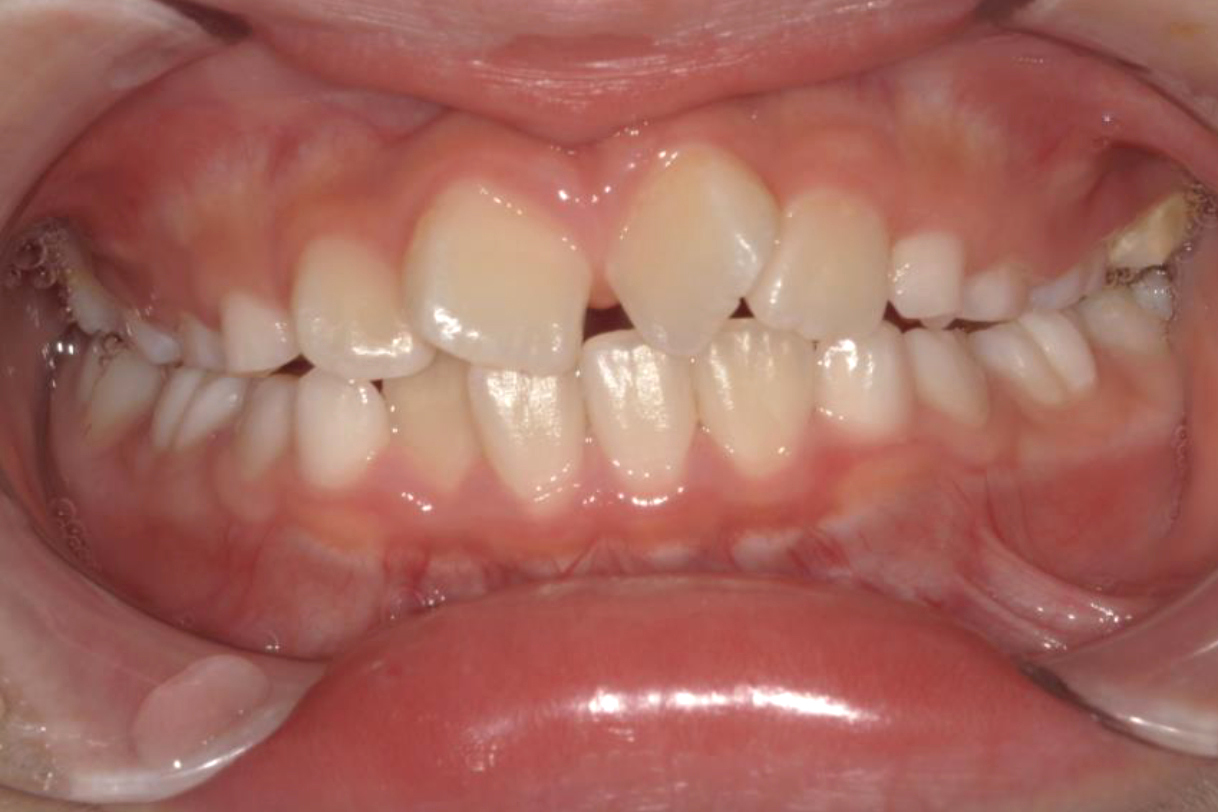

初診時年齢:7歳

治療:前歯部矯正

治療法:上顎前歯部表側の装置

治療期間:2ヶ月

費用:110,000円(税込)

リスク・副作用:装置装着による違和感、歯の移動時の痛み